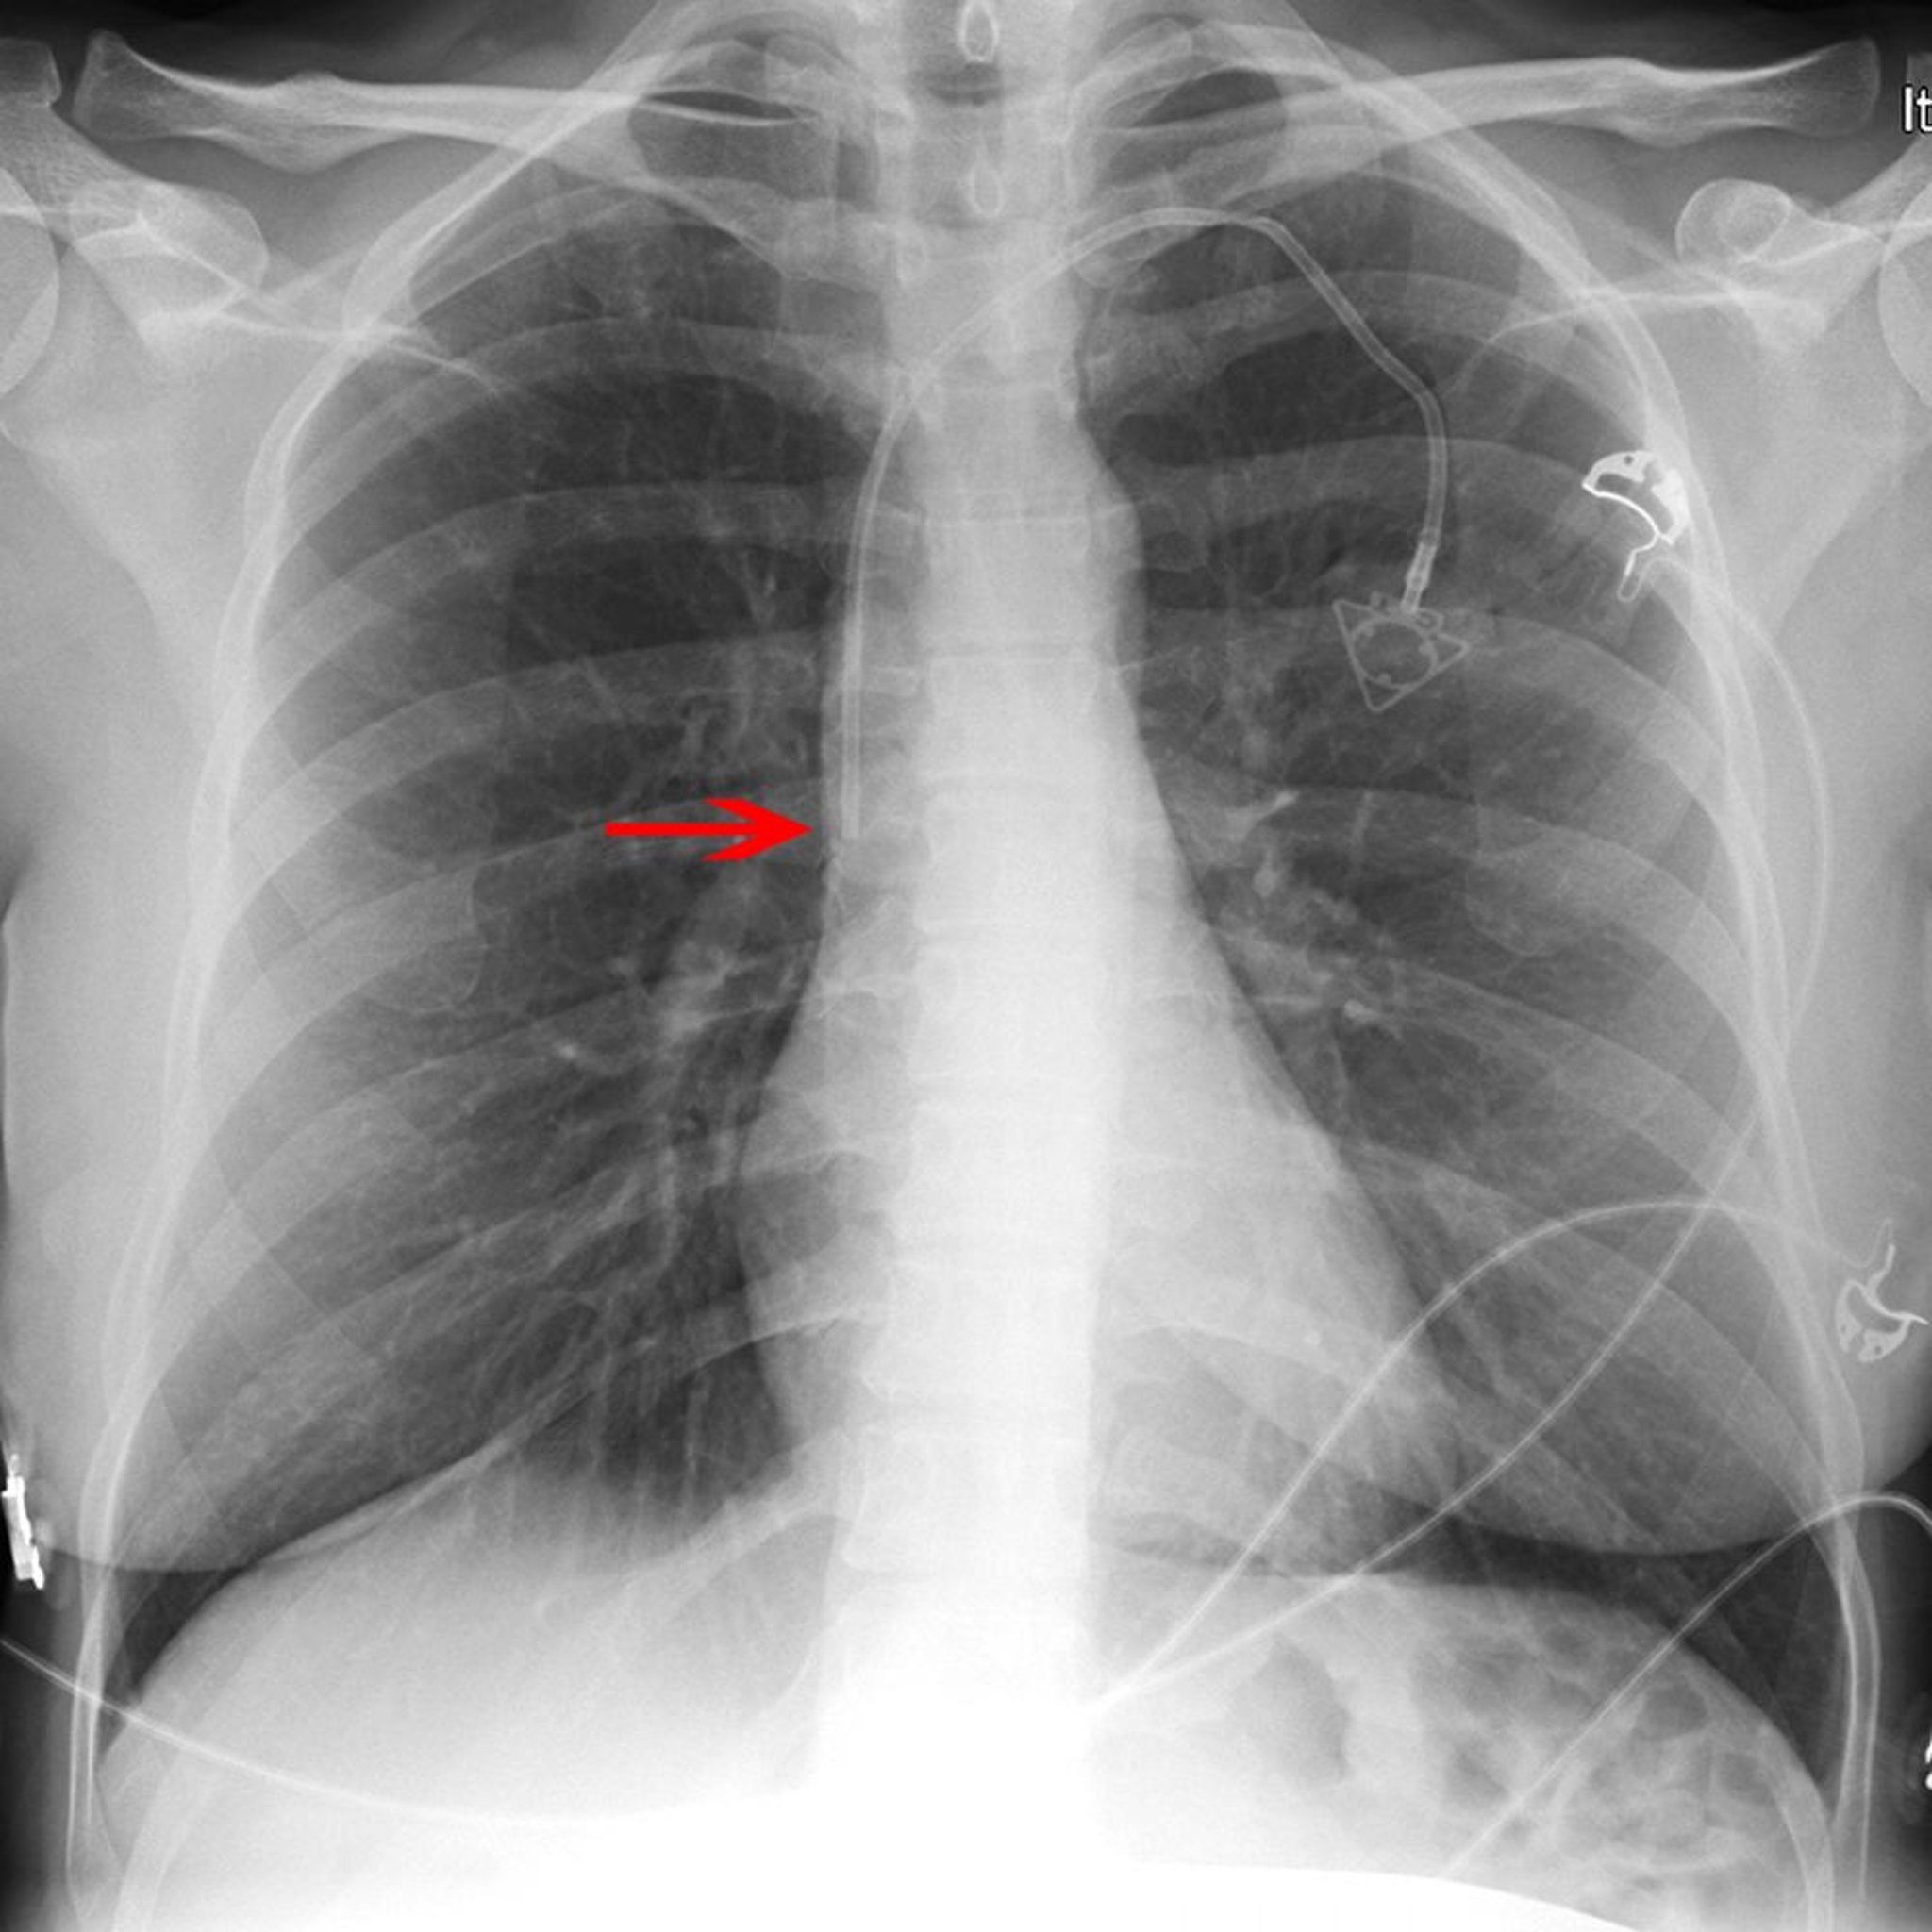

Рентгенограма центрального венозного катетера

The red arrow points to the tip of a left subclavian venous port catheter (placed appropriately in the lower superior vena cava).

© 2017 Elliot K. Fishman, MD.